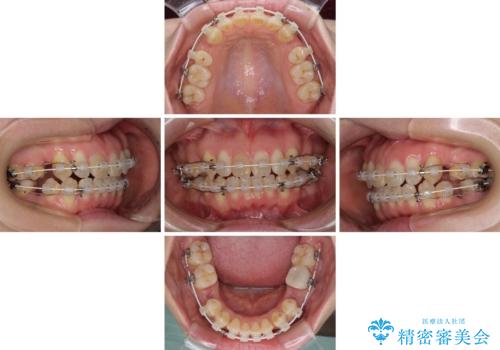

- 矯正装置

- 審美装置

- 治療期間

- 1年9ヶ月

上顎左右第一小臼歯2本、下顎左右第二小臼歯2本を抜歯し、ワイヤー装置にて口元を引っ込めるよう矯正治療を行うこととしました。

上下の前歯に隙間が空くほど上顎前歯が前に飛び出していましたが、抜歯矯正により上下前歯がぴったりと付くほど口元を引っ込めることができました。